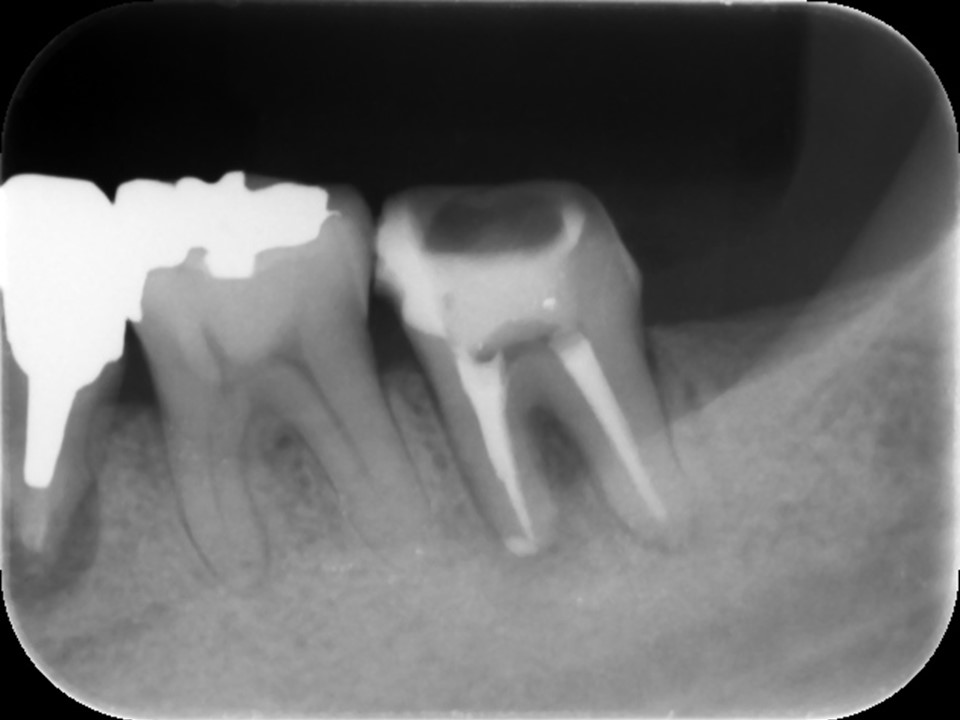

根管充填

破折していたファイルを除去し、根尖部まで完全に根管内を清掃・消毒をして無菌化することで、歯茎の腫れはきれいに消失しました。症状が無く、マイクロスコープで根管内がきれいになっていることを確認し、根管充填を行いました(下写真)。

根管充填では、ペースト状のバイオセラミックシーラーとゴム状のガッタパーチャを用い、根尖まで隙間なくしっかりとお薬を詰めます。

根管充填後のレントゲンおよびCT画像です。根尖までしっかりとお薬が詰まっていることが確認できます。